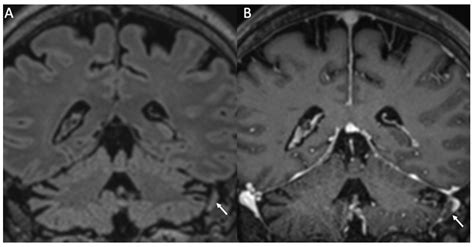

• Imaging tests such as CT scans or MRIs to visualize brain inflammation

• Electroencephalogram (EEG) to detect abnormal brain activity